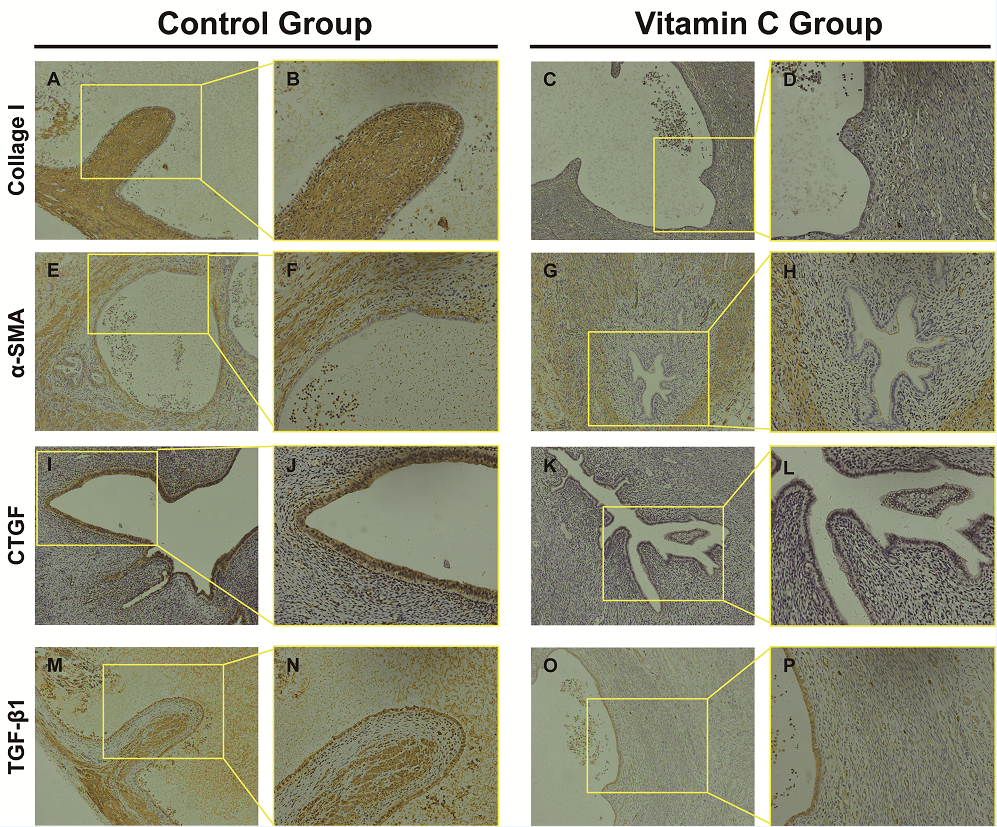

In tissue sections, the degree of fibrosis as highlighted by Masson’s staining of endometriotic lesions was significantly less in the vitamin C group than in the control group (P < 0.05) (Figure 5). Three pathologists blindly examined all tissue sections, and the fibrosis score of the vitamin C group was significantly less than that in the control group (Table 3). Additionally, collagen type I, α-SMA, CTGF, and TGF-β1 expression in immunohistochemical staining was significantly lower in the vitamin C group than in the control group (Figure 6). Moreover, the degree of fibrosis around endometriotic lesions in rats was significantly reduced in the vitamin C group compared with the control group.

Figure 6.

Figure 6.— Comparison the expression of Collagen I, α-SMA, CTGF and TGF-β1 between control and vitamin C groups by immuniohistochemistry. (A and B) Collagen I staining of control group; (C and D) Collagen I staining of Vitamin C group. (E and F) and (G and H) represent α-SMA staining of control group and vitamin C group respectively. (I and J) and (K and L) demonstrate CTGF staining of control group and vitamin C group, respectively. (M and N) and (O and P) represent TGF-β1 staining of control group and vitamin C group, respectively. (A,C,E,G,I,K,M,O: 100×; B,D,F,H,J,L,N,P: 200×).